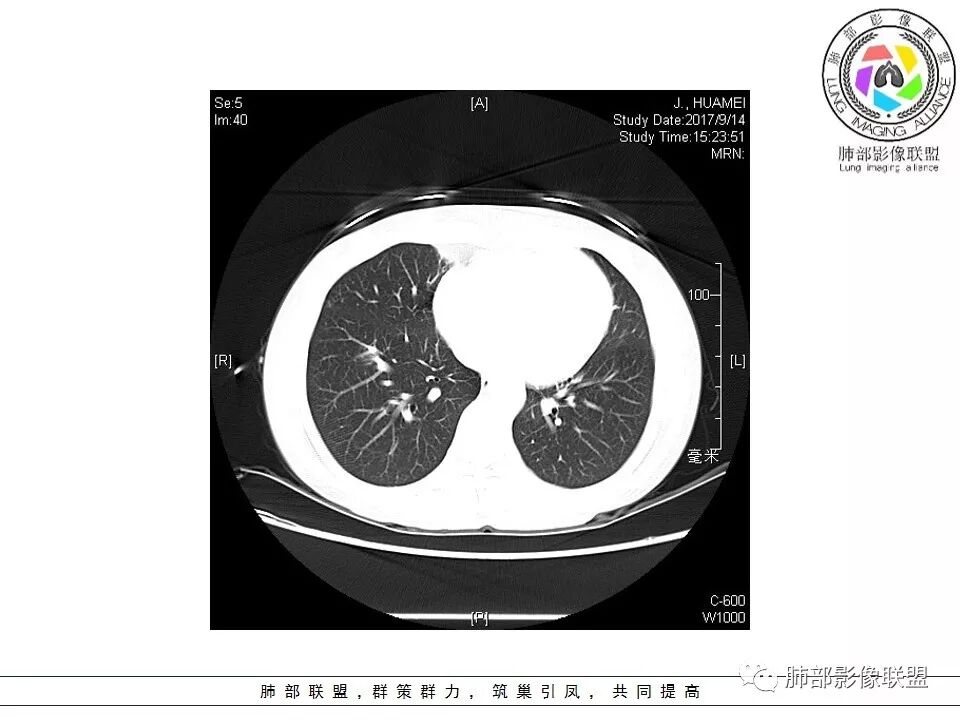

晨读:右肺下叶肿块影,浅分叶,不均匀强化,有血管穿行其中,考虑肺癌,神经内分泌肿瘤可能性大。

右肺下叶结节,边缘毛糙,内支气管推移,有血管贴行,小细胞肺癌?

晨读:右下肺前基底段支气管亚段分叉处占位,密度均匀、中度均匀强化,结节近边缘有支气管、血管穿行,结节边缘较光滑、有细短毛刺、无分叶,结节周围无卫星灶。考虑:PSP,鉴别:小细胞肺癌、不典型错钩瘤

内部支气管扩张,穿行血管形态自然,支持malt。

轻度分叶,支气管穿行,轻中度强化,血管漂浮,考虑MALT

右肺下叶前基底段肿块,边缘不光滑,毛糙,内见充气支气管征,边缘有浅分叶,肿块周围无病灶,排除了结核。增强扫描明显强化,内见血管影,考虑恶性肿瘤。女性,腺癌多见。

淋巴瘤与小细胞癌鉴别,纵隔内没有肿大淋巴结、结节边缘比较毛糙,淋巴瘤放第一位。

病灶呈圆形,轻度分叶,内见血管及支气管影,考虑MALT。

右肺下叶前基底段结节 边缘磨玻璃密度较清 内部支气管扩张,轻中度强化 穿行血管形态自然,支持淋巴瘤。

晨读:右肺下叶肿块影,浅分叶,边界清,轻度均匀强化,血管自然穿行,NSE偏高,考虑小细胞肺癌!

中年女性,右肺下叶前基底段肿块,轻度分叶,有棘样突出,充气支气管征穿行并形成脐凹征。增强扫描中度强化,内见血管影,血管壁毛糙,考虑恶性,腺癌?小细胞肺癌?

晨读,右肺下叶前基底段实性结节,边缘膨隆,可见多发浅分叶,结节内密度均匀,增强后呈轻度均匀强化,血管穿行走形自然,首先考虑恶性肿瘤,内有支气管穿行,淋巴瘤可能大,腺癌待排。

右肺下叶肿块,边缘光滑,浅分叶,膨隆明显,局部有清楚的ggo,考虑恶性,类癌首可能,鉴别腺,PSP。

中年女性,右下类圆形肿块,部分膨胧,边缘浅分叶,脐凹,内见血管穿行,增强轻中度强化,叶间胸膜结节?考虑腺癌,内有支气管穿行,鉴别淋巴瘤。

右肺下叶肿块影,边缘光滑,彭隆,浅分叶,内见支气管通过,增强明显强化,内见血管影,考虑恶性肿瘤,神经内分泌癌,鉴别淋巴瘤。

中年女性,体检发现,病史及化验无特殊。胸部CT右肺下叶前基底段见一类圆形结节,边界清楚,分叶不明显,边缘呈锯齿状改变,病灶内支气管穿行,无扩张及扭曲,增强扫描病灶明显均匀强化,内见穿行血管影,走形无扭曲。考虑粘膜相关性淋巴瘤可能。鉴别炎性假瘤、腺癌及小细胞癌。

患者中年女性,因“体检发现右下肺占位4天。”入院,肿瘤标记物NSE轻高。

胸CT:右肺下叶前基底段占位性病变,内可见支气管穿过,病灶边缘不规则,呈浅分叶,未见明显毛刺。纵隔窗可见病灶密度相对均匀,增强可见病灶强化,内可见血管增粗,边缘模糊,总体考虑恶性,腺?。良性疾病鉴别错构。

右下肺类圆形实形结节,边缘膨隆,浅分叶,其内可见支气管及血管影走行,轻度强化,考虑恶性病灶,淋巴瘤?类癌?

边缘彭隆,还是考虑肿瘤,支气管通入,肺内原发,支气管自然穿行稍扩张,血管比较自然同行,漂浮征,增强后整个比较均匀无明显坏死,淋巴瘤首选。恶性应该没有问题,建议穿刺。

这个病灶边缘还是有一点点恶性征象,有分叶,似乎有点地方还有一些小毛刺样感觉

部分区域整体以膨隆为主,部分区域稍收缩

内部支气管走形非常自然,达远端稍扩张;内部血管穿行也非常自然

内部密度比较均匀,我们一般来说,首先良性肿瘤不支持,因为它里面的血管走形太自然了;然后就是炎性病变跟恶性肿瘤,但是它的边缘膨隆比较厉害,有些地方还毛刺,不是很清楚,倾向一个恶性病变

恶性的血管穿行自然,包括支气管稍扩张,最常见还是淋巴瘤,它强化比较均匀;

粘液腺癌一般支气管扩张比较罕见,这个密度及强化太均匀,不是很符合,所以把淋巴瘤放前面,癌待排;

方向定在恶性的,炎性病变不是很符合